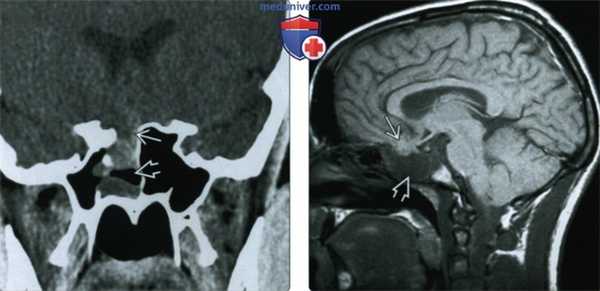

(Слева) МРТ, Т2-ВИ, сагиттальный срез (приобретенное лобно-решетчатое энцефалоцеле): выпячивание нижних отделов лобных долей через дефект передних отделов основания черепа в решетчатую пазуху. Изначально было проникновение крючка от амортизирующего троса через нос в лобные отделы передней черепной ямки, лечение данного состояния было выполнено нехирургическим способом.

(Справа) Корональный КТ, костное окно (приобретенная лобно-решетчатое эн цефалоцеле): у пациента с посттравматической ликвороринореей определяется срединный костный дефект продырявленной пластинки/передней черепной ямки. (Слева) МРТ, Т1-ВИ, сагиттальный срез (затылочное эн цефалоцеле): выпячивание дисморфичных затылочных долей в грыжевой мешок заднего цефалоцеле. Мозжечок деформирован, но не заходит в описанный мешок. Костный дефект не распространяется на большое затылочное отверстие, что указывает на высокий затылочный вариант цефалоцеле.

(Слева) При КТ с КУ в корональной проекции у пятидневного младенца с объемным образованием носовой полости определяется транссфеноидальное цефалоцеле, пролабирующее в носоглотку через обширный дефект основания черепа. На этой томограмме видно, что цефалоцеле содержит преимущественно спинномозювую жидкость, но при исследовании содержимого грыжевого мешка более информативна МРТ.

(Справа) При КТ с КУ в аксиальной проекции у этого же ребенка наблюдается гипертелоризм, вызванный пролабирующим через дефект основания черепа цефалоцеле, и выраженная колобома зрительного нерва.

(Слева) При КТ без контрастного усиления в корональной проекции у подростка определяется дефект верхней стенки частично затененной правой клиновидной пазухи. В этом случае дефект черепа возник в результате перенесенной травмы головы, у пациента наблюдалась посттравматическая ликворея.

(Справа) При МРТ Т1ВИ в сагиттальной проекции у этого же пациента значительно лучше визуализируется содержимое пролабирующею через дефект основания черепа в клиновидную пазуху цефалоцеле - ткань задне-нижней части лобной доли и большое количество спинномозговой жидкости.